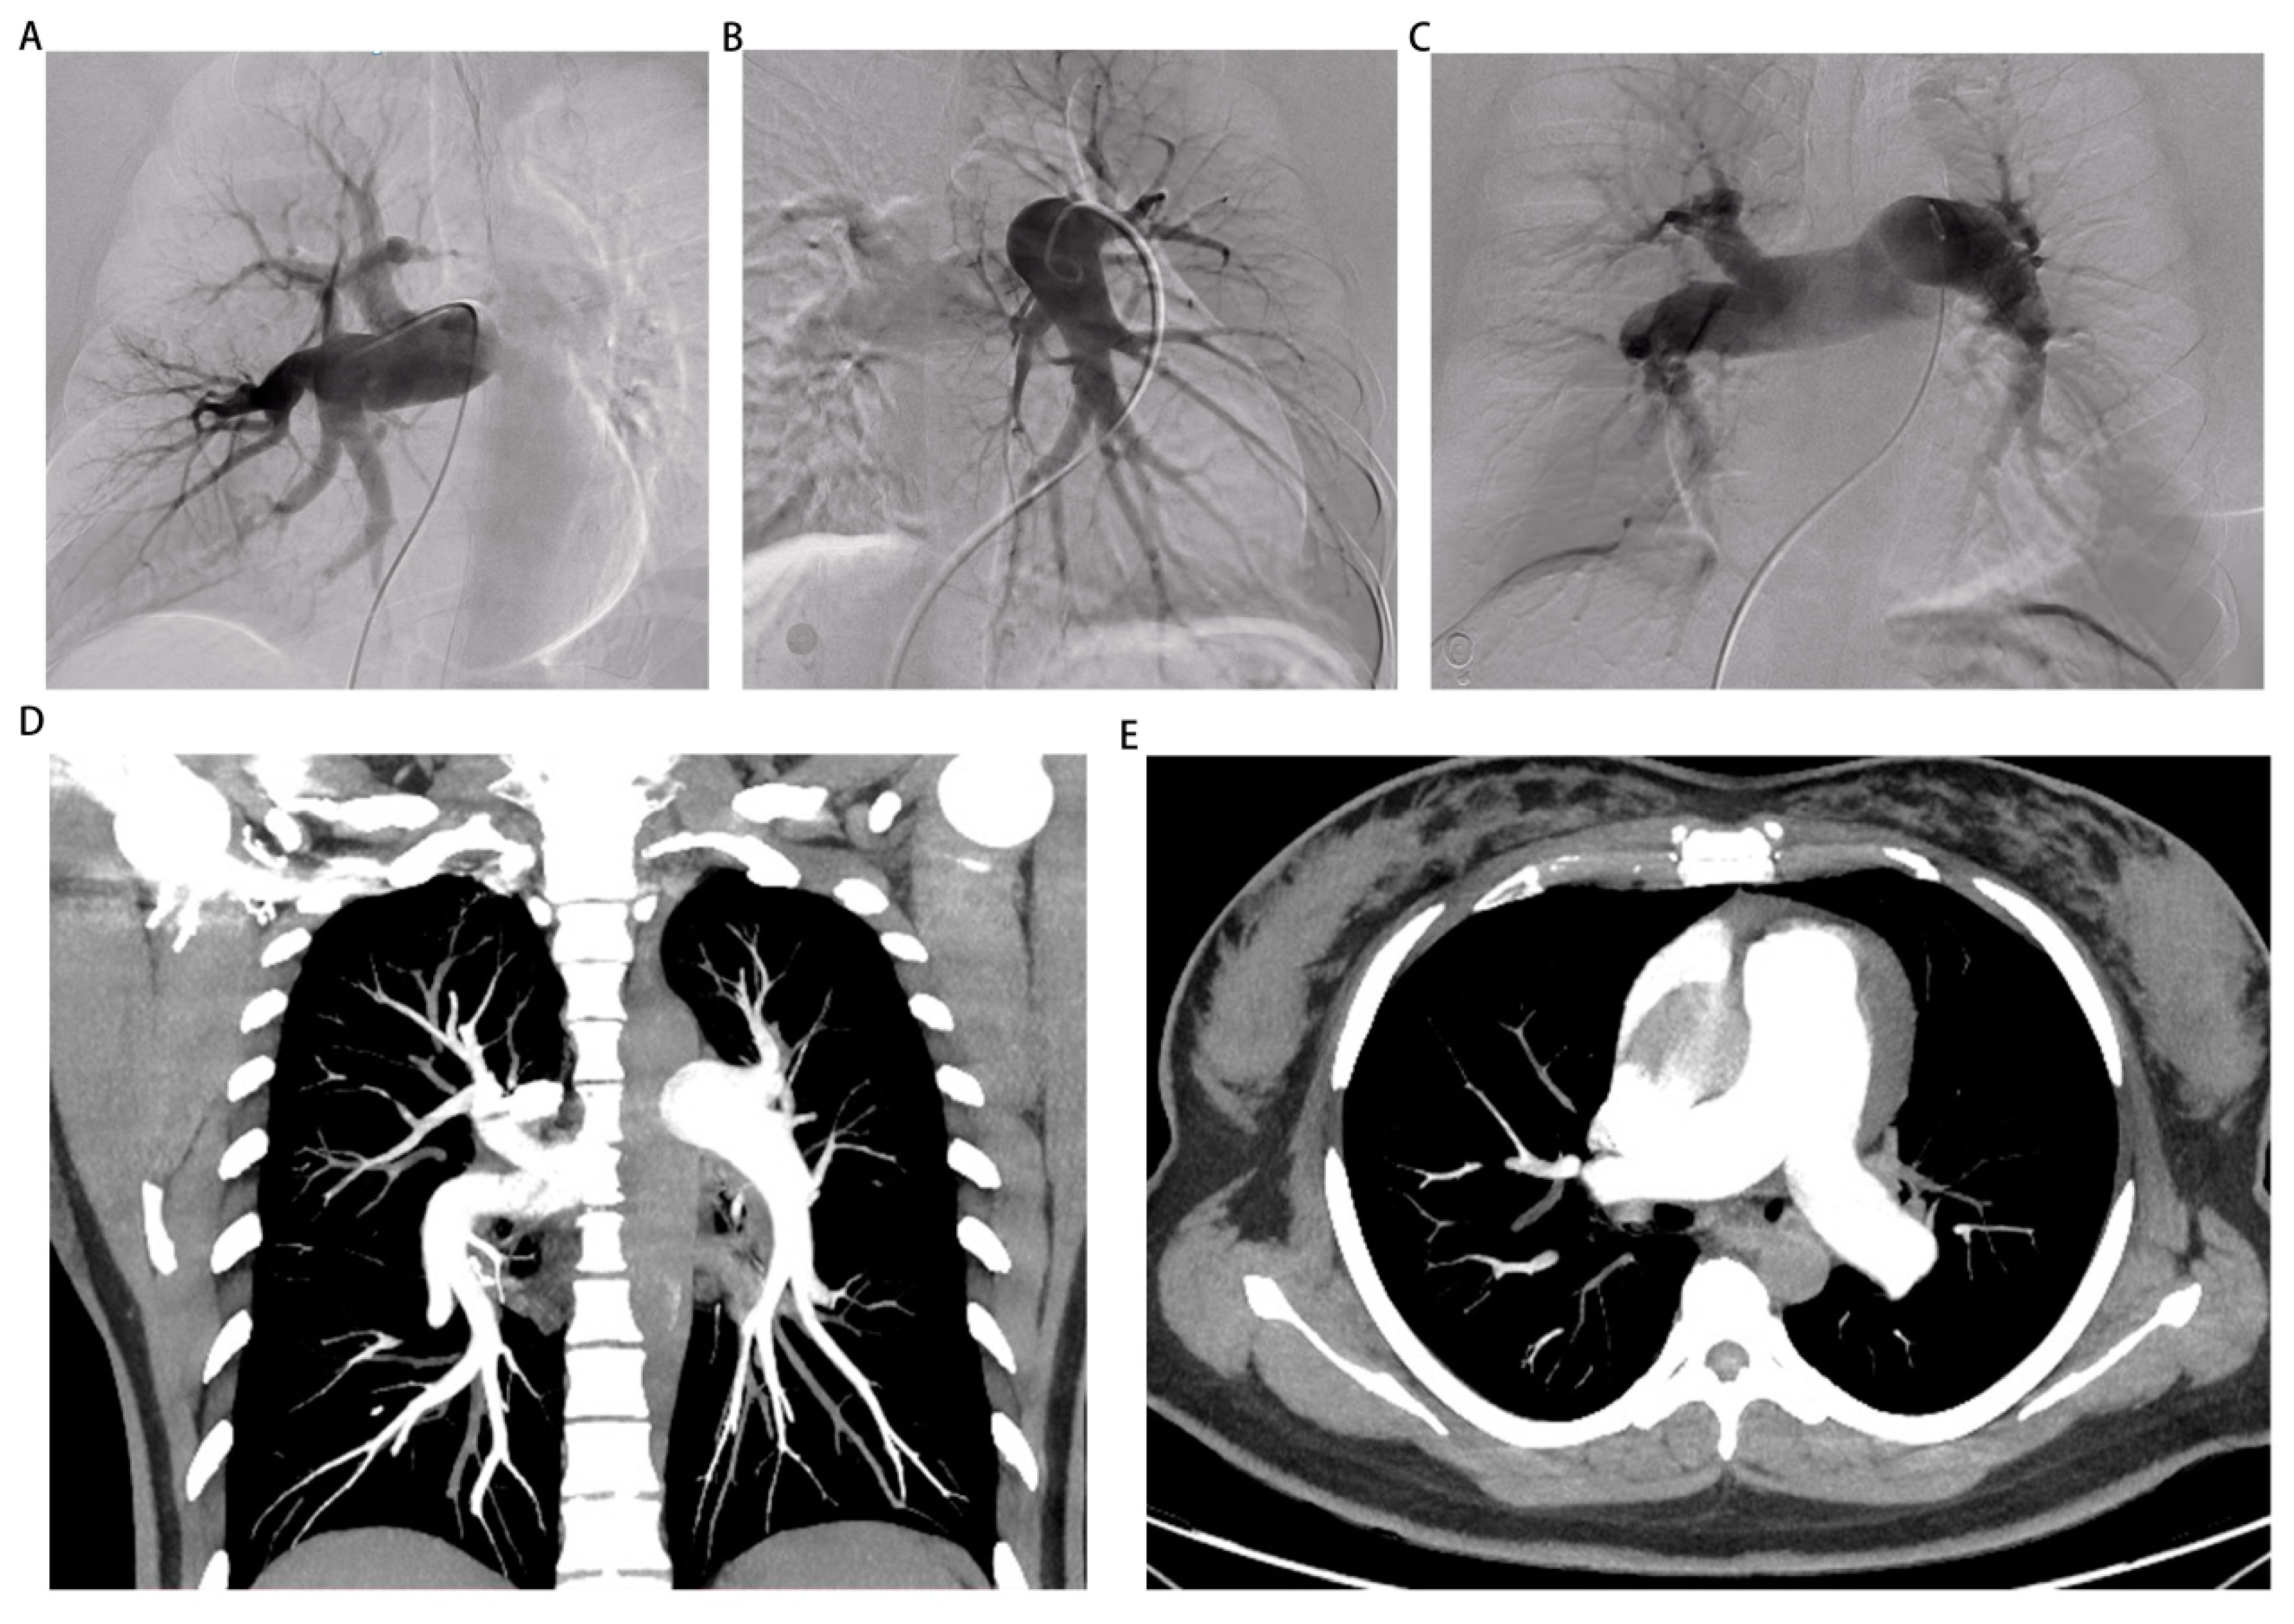

Figure 1. Manifestations of computed tomography pulmonary angiography, electrocardiogram, X-ray and pulmonary perfusion imaging on admission. Pulmonary computed tomography angiography conducted by external hospital indicated the presence of pulmonary artery dilatation. (B) Electrocardiogram showed q wave in lead V1 and right deviation of the electrical axis upon admission. (C) Chest X-ray demonstrated enlargement of the heart shadow. (D) Pulmonary perfusion imaging revealed the presence of multiple perfusion defects in both lung fields, with the left lung showing a more severe impairment than the right.

Upon admission, a twelve-lead electrocardiogram (ECG) indicated the presence of a q wave in lead V1 and right deviation of the electrical axis (Figure 1B). Additionally, a pulmonary computerized tomography (CT) scan revealed poor ventilation in the upper lobe of the left lung. Besides, a chest X-ray demonstrated enlargement of the heart shadow (Figure 1C). On the first day of hospitalization, TTE revealed left atrial and right heart enlargement(La, 36 mm; Ra-L, 74.3 mm; Ra-M, 53.4 mm) with left ventricular ejection fraction of 62%, a dilated main pulmonary artery (26.8 mm), and severe regurgitation of the tricuspid valve, with an estimated pulmonary artery systolic blood pressure of 95 mmHg(Supplementary video 2-5). The abdominal ultrasound examination revealed an augmented inner diameter of the inferior vena cava, which indicated right heart failure. In the case of severe heart failure, a combination of bumetanide and spironolactone was used for treatment. Considering the presence of postpartum severe PAH, a decision was made to initiate sildenafil at a dosage of 12.5 mg thrice daily to mitigate pulmonary artery pressure.

According to the findings from previous echocardiography, there was an absence of manifestations of structural heart disease in the patient under examination. Furthermore, the patient exhibited normal left heart diastolic and systolic functions. Consequently, it is improbable that the patient's pulmonary hypertension can be attributed to left heart disease. Additionally, pulmonary perfusion imaging was conducted, revealing the presence of multiple perfusion defects in both lung fields, suggesting a more severe impairment in the left lung (Figure 1D). In this particular case, it was necessary to establish a differential diagnosis for pulmonary embolism. To achieve this purpose, the patient underwent computed tomography pulmonary angiography (CTPA) and was promptly administered prophylactic anticoagulation therapy. Subsequently, the CTPA images revealed an enlargement of the pulmonary artery without any apparent filling defect, thereby contradicting the diagnosis of pulmonary embolism (Figure 2D,E and Supplementary video 10).